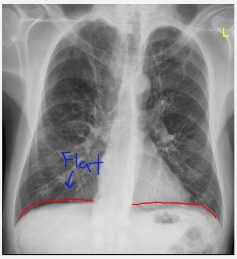

what abnormalities?

-Hyperinflation, FLAT diaphragms

-Vascular markings DECREASE

-Parenchymal bullae

COPD: is it chronic bronchitis or emphysema?

emphysema: